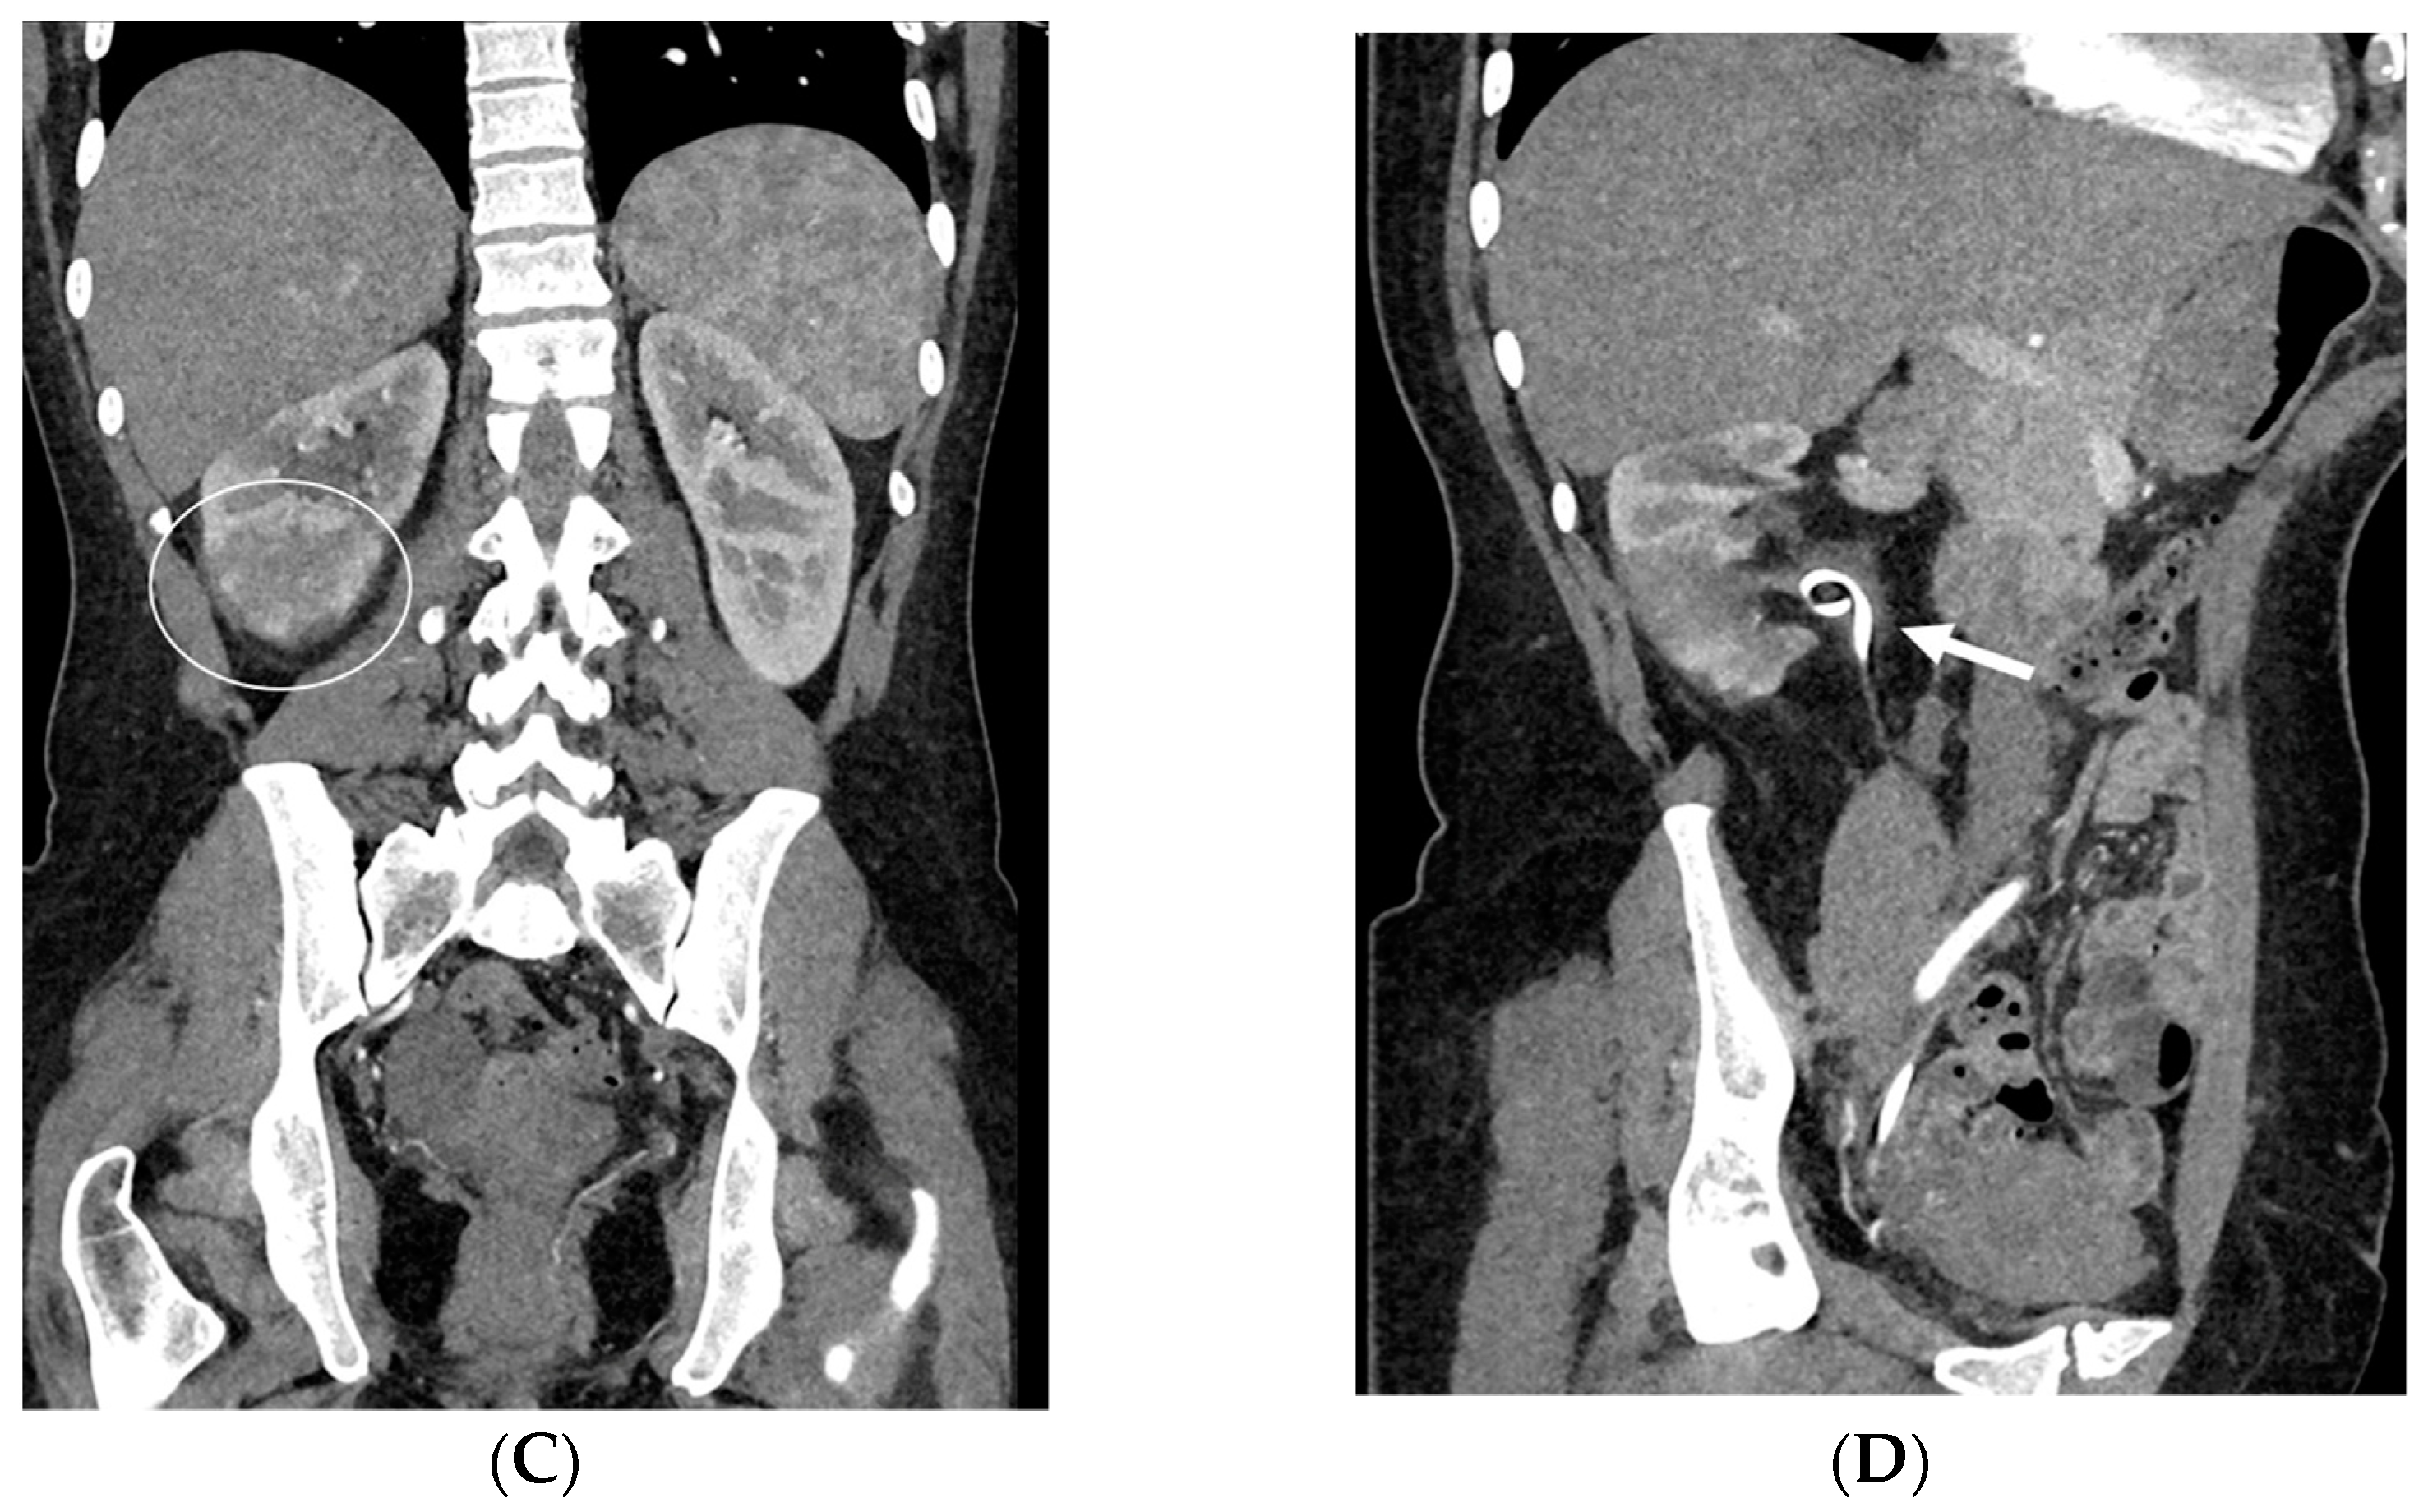

- Bleeding: The erosion of the stent into the arterial system is a rare and feared complication of ureteral stent placement, which can cause hematomas (Figure 10 and Figure 11), active bleeding, or pseudoaneurysm (Figure 12, Figure 13 and Figure 14). To avoid mortality from these complications, a high level of clinical suspicion is essential. Intermittent hematuria in a patient with a stent is typically the usual clinical scenario. However, massive hematuria and circulatory collapse can occur due to the manipulation of the ureteral stent [2,39].